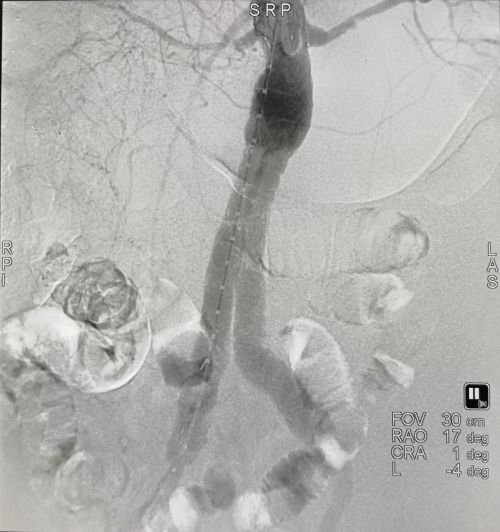

腹主动脉破裂出血。

覆膜支架腔内完美修复破裂瘤体。

谁知,刘某刚躺上手术台便突发腹主动脉瘤二次破裂,血压趋于零,生命危在旦夕。在大剂量的升压药和快速输血情况下,血压勉强维持在60/40mmHg,情势仍然十分危急。王庆带领该院介入血管外科团队在20分钟内完成复杂的腔内修复治疗,出血立即停止,患者生命体征趋于稳定。